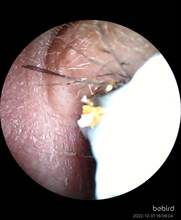

Are you getting sick of useless Q-tips that can’t clean your ears? Also, they can be dangerous because you can’t see where you’re poking at, it’s easy to hurt your ears! So, may I introduce to you the Smart visual ear wax remover, a system to keep your ears clear and safe. With high technology, this product supports HD live streaming over Wifi through our application. It has six ultra-bright LEDs to light up the entire ear canal, promoting perfect visibility and control. Moreover, with five unique brightness levels, this ear cleaner can support crystal clear videos from inside your ears. All of that to make your earwax removal safer than ever. Also, the App supports both iOS and Android devices to connect, so it’s convenient for everybody. Don’t hesitate anymore, get it now!

Rapid WiFi visual connection. No connection is required to open picking ears. Use optical lens and high performance 300W pixel. The CMOS sensor has a clear picture, 20X amplifying ear canal & 55° viewing angle. 13 lens combination & 6 LED lights. IP67 waterproof lens. Water washable. Adapt to dry ear, oil ear and other complex environment. 3 axis smart directional gyroscope quick positioning, screen is not bias & shake. High-end OV chip video coding technique, hand-eye synchronous exciting picking! Strong WiFi signal, penetrating power, avoid delay. More safety protection. Earpick head buckle, over-hot earpick protection, timing automatic shutdown, children lock and anti frost cracking protection. Smart constant temperature control. Prevent low temperature & ear burning . Otoscope: 25°C non-inductive temperature. Earpick body: 32°C palm’s temperature. Long endurance. Built-in 250mAh large capacity battery. Picking once a week for 10 minutes, can use about 30 days.

A wonder, I could remove wax from a long time ago it's amazing thank you very much